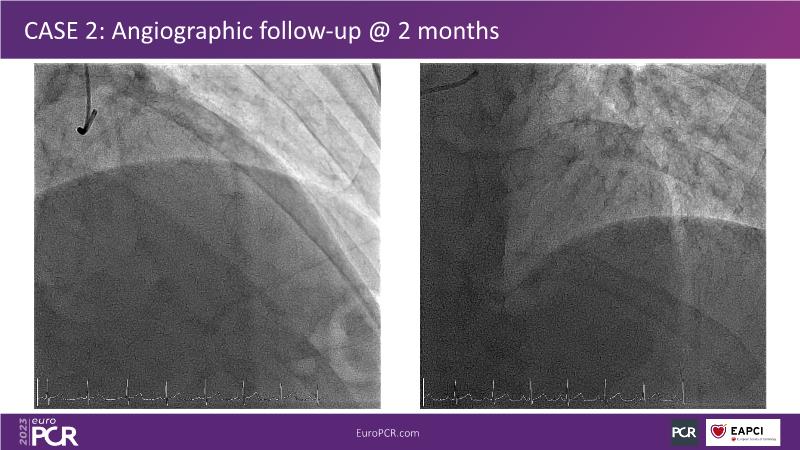

Next generation of DES technology, what it's all about? Find out in this session where experts will present complex cases from around the world and discuss the new indications for which they can be used.

• To know why and how a fusion coating of DES+DCB stent platform is effective for the treatment of cardiovascular disease in diabetes mellitus patients via case presentations

• To understand why you can count on customised drug delivery platform of DES+DCB in complex settings with imaging-based evidence through case presentations